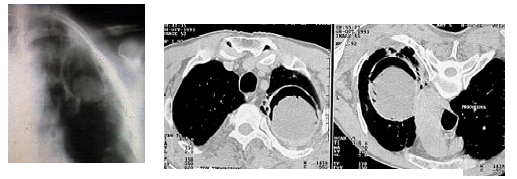

- U nấm điển hình: tổn thương hình lục lạc gồm một hốc rỗng trong có chứa khối nấm đặc và một liềm khí ở phía trên của khối nấm.

♦ Chụp cắt lớp vi tính ngực: cho phép phát hiện rõ hơn tổn thương hang nấm hình lục lạc với liềm hơi ở phía trên có thể có kèm theo hoặc không các tổn thương khác: xơ co kéo, thoái hóa dạng kén, dày màng phổi nếu tổn thương sát màng phổi, đôi khi có hình ảnh calci hóa trong khối nấm.

Hình ảnh u nấm trên phim CT ngực trên cùng một bệnh nhân ở hai tư thế khác nhau (A: tư thế nằm ngửa, B tư thế nằm sấp). Liềm khí trong hang nấm luôn ở phía trên của hang.